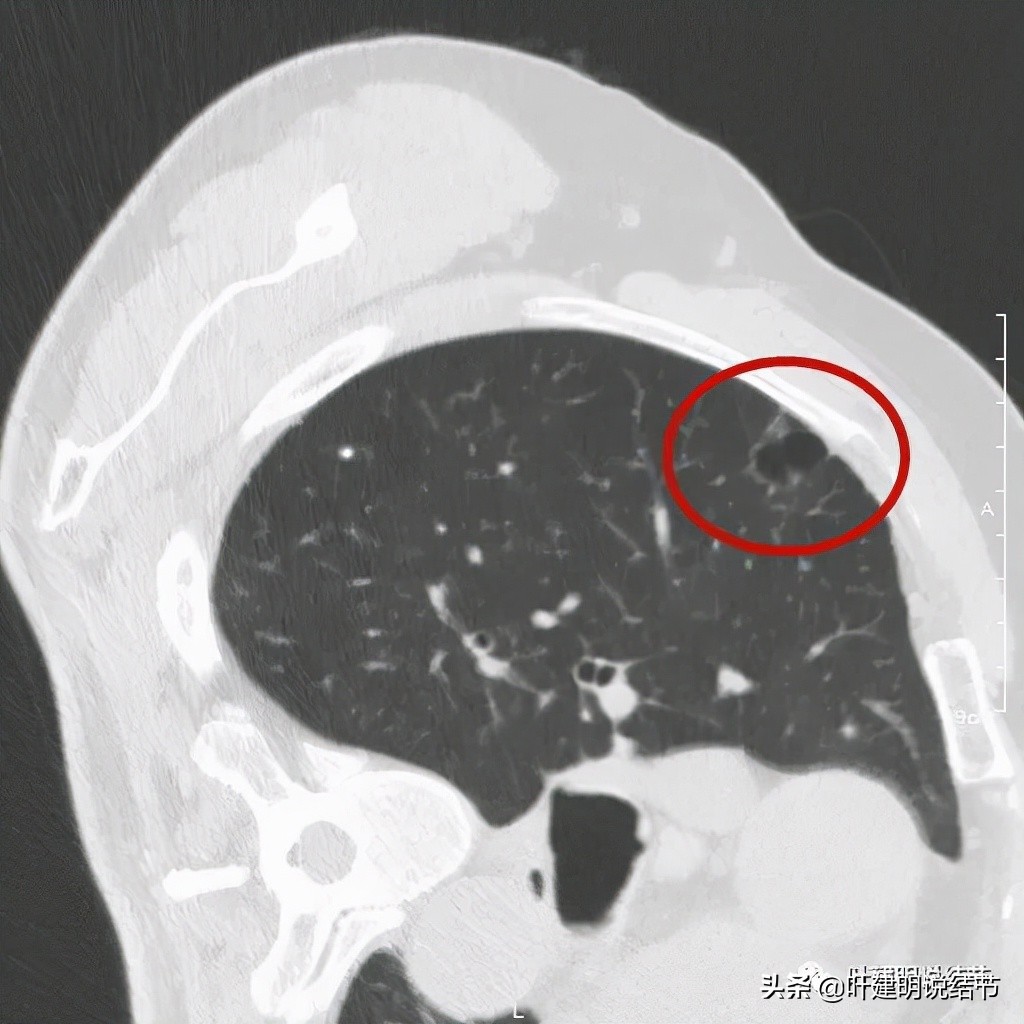

以上诸图是病灶4:考虑囊腔型肺癌可能性大,壁厚薄不均,内壁不光滑,有血管进入病灶,有少许密度偏高的成分,但纵隔窗上未见,不是真正意义上的实性成分。

感觉怎么囊壁实性成分密度有点显得高,粉色箭头所示处明显密度不均,偏高密度;蓝色箭头示有胸膜牵拉;砖色箭头示分叶征;桔色箭头示血管走向病灶。我觉得关键是病灶位置好,紧贴胸壁,能局部楔形切除,对肺功能影响小,又能去除危险。倾向切了它!

上面是去年6月与11月时的对比,变化是不是太明显的。也许心理作用,感觉11月的略微饱满点。关键的是某A自己觉得活动耐力明显较之前已经有改善了,日常活动没有明显影响了。再查肺功能与血气分析: